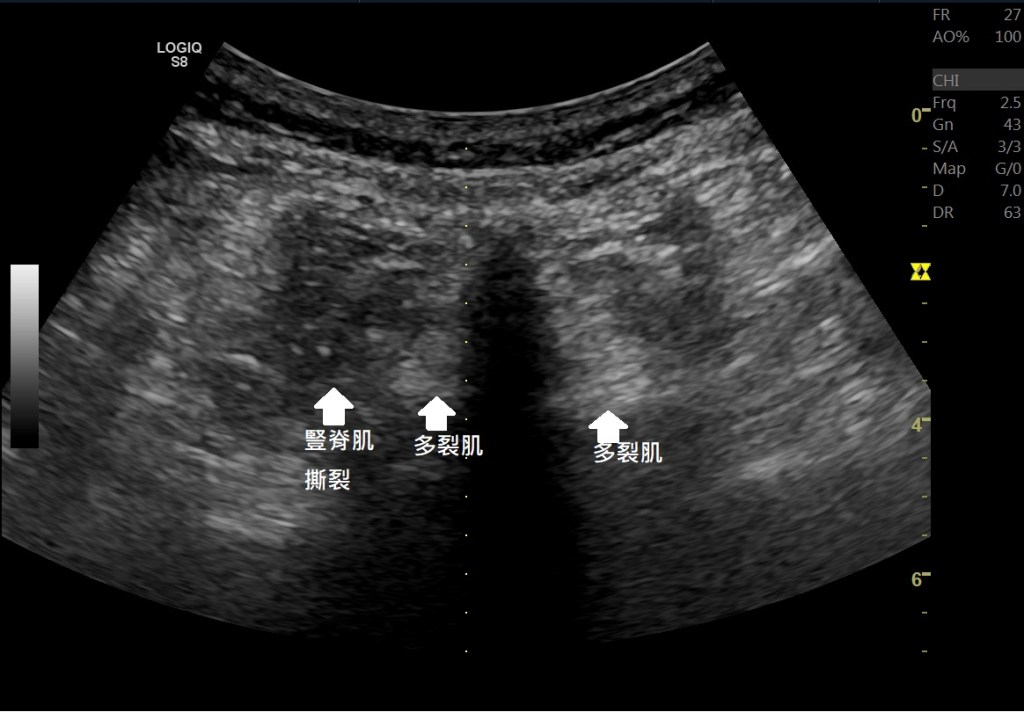

在超音波底下除了可以看到小面關節骨刺、韌帶撕裂、韌帶鈣化等等著病徵,甚至在肌肉層也會有一些變化。例如多裂肌的纖維化(Fatty fibrotic change)、豎脊肌的撕裂,這些都跟脊椎滑脫有關。